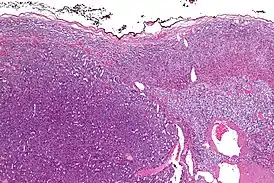

Адренокортикальный рак (англ. adrenocortical carcinoma) — редкая злокачественная опухоль, исходящая из коркового слоя надпочечника[1]. Встречается с частотой 2-4 случая на 2 миллиона населения[2].